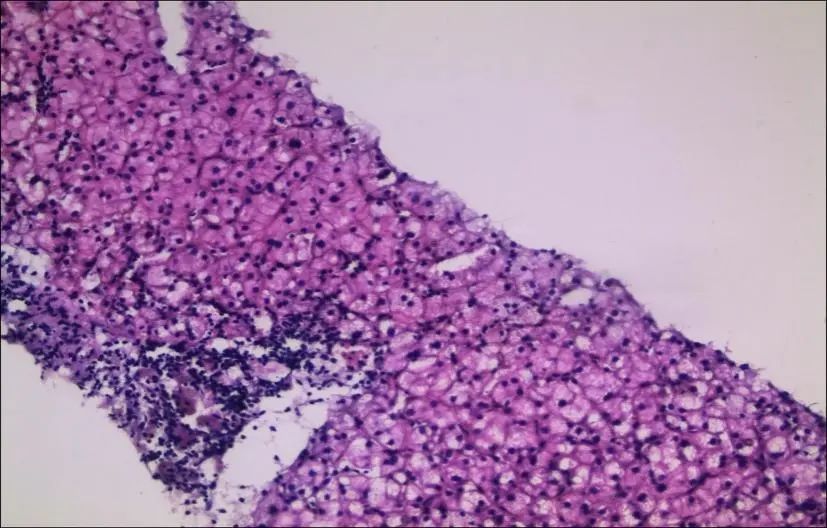

患者因腹胀伴牙龈出血为主要临床表现,院外检查提示显著脾大,因压迫腹腔脏器,导致腹胀;而脾功能亢进可致血小板计数(PLT)下降明显,继之引起反复牙龈出血;但腹部CT仅提示早期肝硬化表现,且行胃镜未见食道胃底静脉曲张,因此用乙肝后肝硬化门静脉高压所致脾大、脾功能亢进与临床表现提示的门静脉高压性病变不符;故行肝穿刺活检,病理(肝组织)示:符合中度慢性病毒性肝炎,G2/S2-3;免疫标记:HBsAg胞膜(+)、HBcAg(–),免疫表型显示病毒活跃复制状态仅提示中度慢性病毒性肝炎(图1),未见假小叶形成,可排除肝硬化及肝源性脾大。

图1. 肝穿:肝脏组织结构正常,广泛性肝细胞水肿,肝窦内少量淋巴细胞浸润;汇管区胆管形态、结构正常,间质较多淋巴细胞浸润伴中度界面炎改变